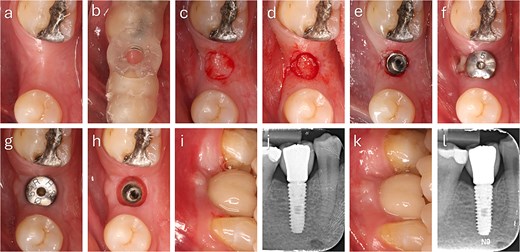

The punched graft was stabilized with corn tweezers and deepithelialized using a #15c blade (Supplementary Video S1). A buccal pouch was created with a Kirkland knife and tunnelling instruments, and the graft inserted with orientation adapted to thickness: in thin grafts (Fig. 2), the connective surface faced the implant; in thicker grafts (Fig. 3), it was oriented apically. A healing abutment coated with chlorhexidine–hyaluronic gel supported graft stabilization without sutures. A definitive crown was placed after 48 hours of implant placement in immediate loaded case.

Clinical sequence of buccal augmentation with deepithelialized punched tissue during immediate implant loading. The graft was incorporated successfully, with stable peri-implant tissues at six months. (a, b) Preoperative occlusal and lateral views with atrophic ridge and retained root. (c) Occlusal view after extraction. (d) Surgical guide in position. (e) Harvested keratinized punched tissue. (f) Scan body placement. (g, h) Graft insertion and tissue former placement. (i) Crown delivered at 48 hours. (j) Radiograph after crown placement. (k) Six-month follow-up with healthy peri-implant mucosa. (l) Radiograph at 6 months showing no bone loss.